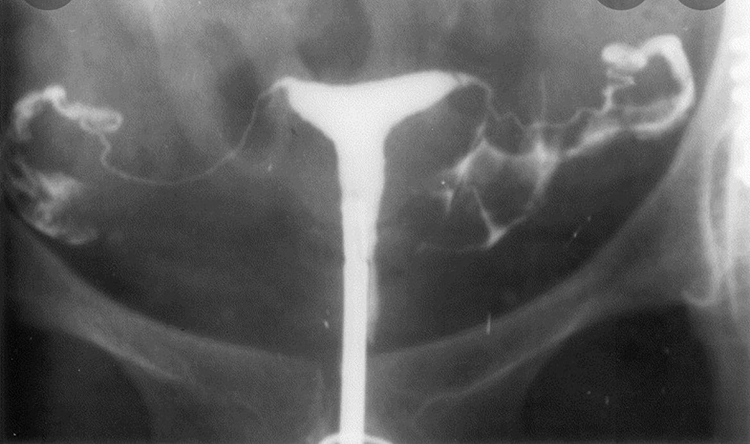

Медицинские снимки: Проходимость маточных труб

Раздел: Кадры-подсказки